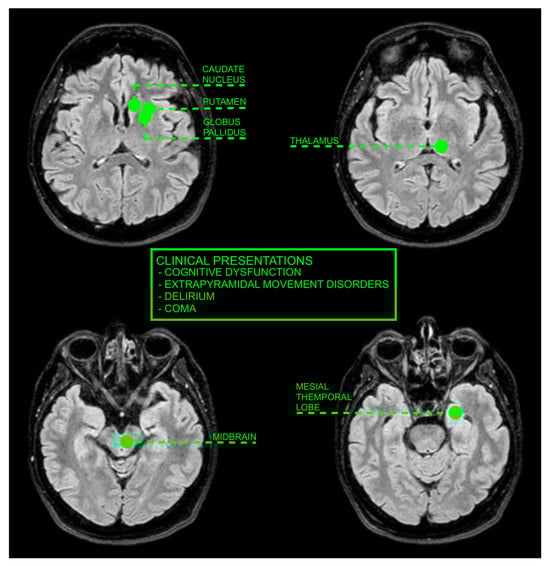

| Wang et al. [19] | 2003 | Taiwan | Clarify the clinical spectrum and possible pathophysiology of UE with BG involvement | 6 | BG lesions in uremic patients are associated with acute movement disorders and are not uncommon. The pathophysiology remains unclear. |

| Lee et al. [20] | 2007 | Republic of Korea | Investigate acute bilateral BG lesions in diabetic uremic patients | 4 | Bilateral BG lesions are primarily vasogenic, with some foci of cytotoxic edema. Lesions and symptoms are reversible post-hemodialysis. |

| Wang et al. [21] | 1998 | Multiple | Report on acute and subacute extrapyramidal movement disorders in uremic patients with BG lesions | 3 | UE with BG lesions leads to movement disorders and is linked to hypoperfusion and toxin vulnerability of the BG. |